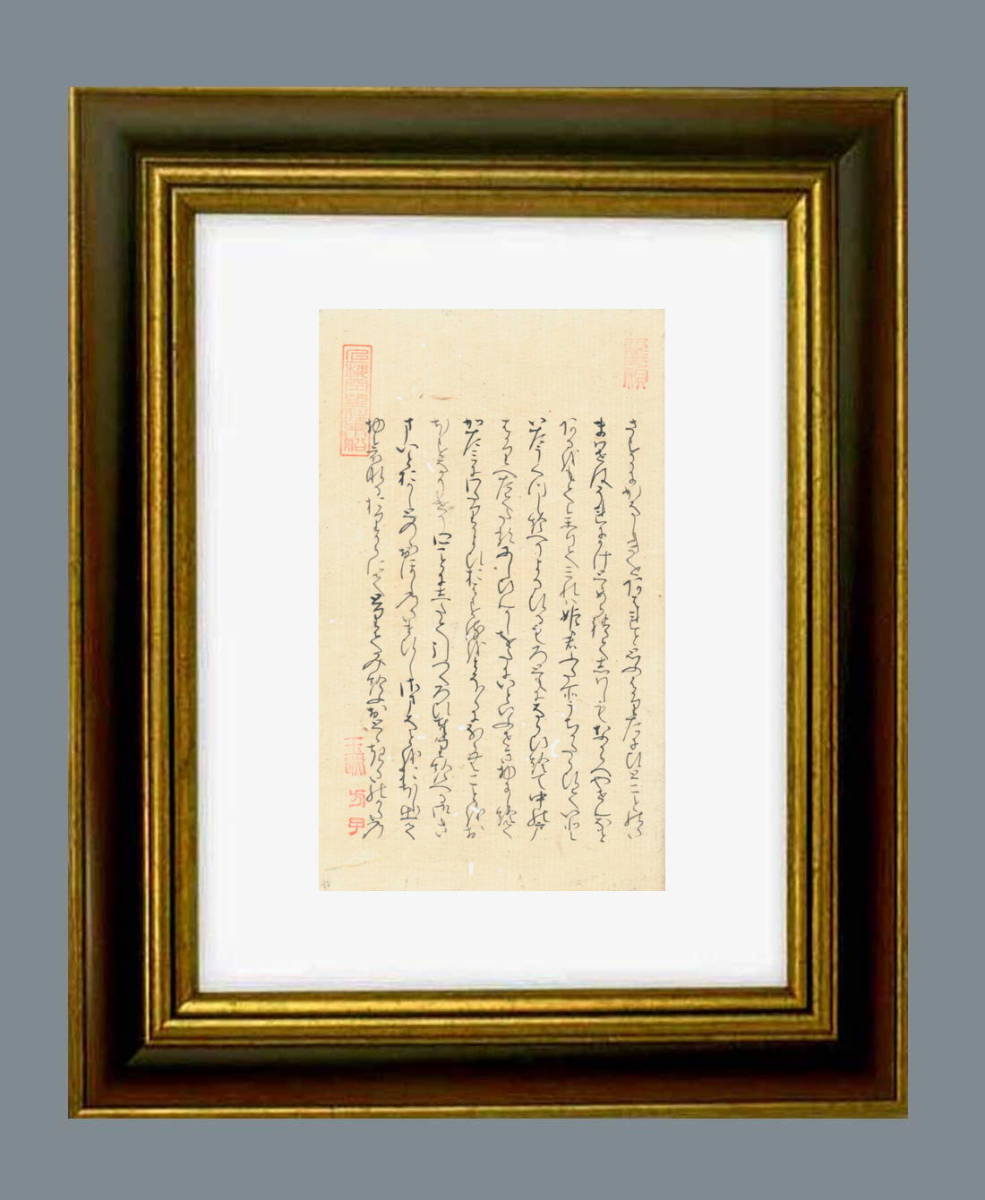

画像診断 12年1月号 32ー1 特集:MRIアーチファクトの光と影

■出版社■

学研メディカル秀潤社

■著者■

■発行年■

2011/12/22

■ISBN10■

4780900263

■ISBN13■

9784780900262

■コンディションランク■

良い

コンディションランク説明

ほぼ新品:未使用に近い状態の商品

非常に良い:傷や汚れが少なくきれいな状態の商品

良い:多少の傷や汚れがあるが、概ね良好な状態の商品(中古品として並の状態の商品)

可:傷や汚れが目立つものの、使用には問題ない状態の商品

■コンディション詳細■

書き込みありません。画像診断|株式会社Gakkenメディカル事業部。[A12347842]NeuroICUブック。水濡れ防止梱包の上、迅速丁寧に発送させていただきます。